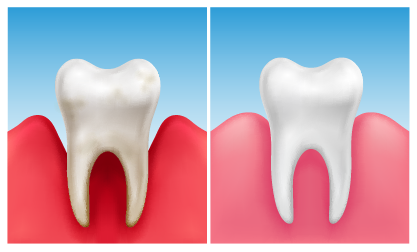

A gengivite crônica é a inflamação da gengiva que, se não tratada, pode evoluir. Ela acontece pelo acúmulo de placa bacteriana. Isso causa vermelhidão, inchaço e até sangramento ao escovar os dentes. Ignorar pode levar a problemas mais sérios, como a periodontite, que afeta os ossos que sustentam os dentes.

A gengivite crônica pode parecer uma coisa pequena, mas se não for tratada, ela pode se agravar e trazer outros problemas. É aquela inflamação persistente que deixa a gengiva inchada e às vezes sangrando. O principal culpado? Acúmulo de placa bacteriana. Pois é, aquela sujeirinha que não sai com uma escovação básica. Precisamos ser mais eficientes na limpeza diária.

O tratamento em casa foca em eliminar a placa bacteriana de forma completa. Isso significa escovar os dentes com atenção, especialmente na linha da gengiva, e usar o fio dental todos os dias, sem exceção. A persistência é chave para reverter o quadro. Lembre-se que a prevenção é sempre o melhor remédio, mas quando a gengivite aparece, a dedicação à higiene é o que vai fazer a diferença.

Vamos combinar: manter uma boa higiene bucal é fundamental para a saúde geral. A raspagem manual entra como um reforço nesse cuidado diário. Ao remover a placa de forma consistente, você diminui a inflamação da gengiva e previne que a gengivite crônica piore.

A gengivite crônica se caracteriza por uma inflamação persistente na gengiva, que fica vermelha, inchada e pode até sangrar com facilidade. Muitas vezes, a causa é o acúmulo de placa bacteriana que não foi removida corretamente com a escovação e o fio dental. Quando ela se torna crônica, os cuidados caseiros podem não ser suficientes para reverter o quadro, e a ajuda profissional se torna indispensável.